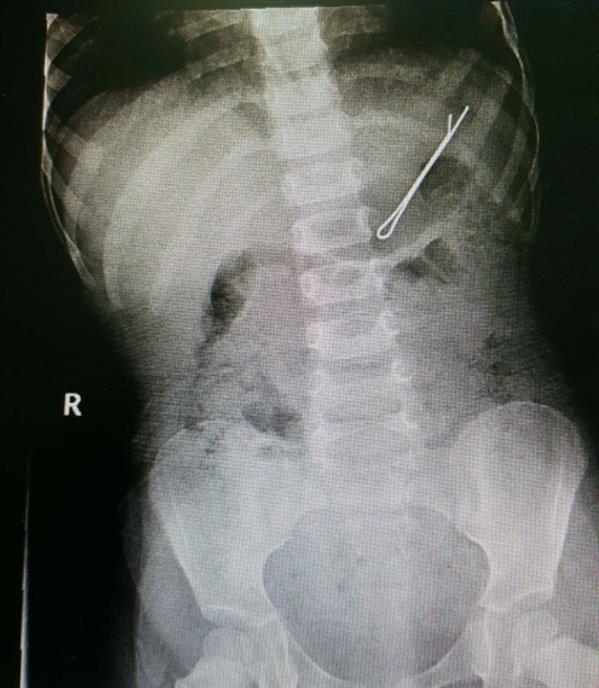

تمكن الفريق الطبي بوحدة مناظير الجهاز الهضمي بمستشفى الولادة والأطفال في بريدة، من استخراج مشبك شعر من معدة طفل يبلغ من العمر سنتين.

وأوضح رئيس وحدة مناظير الجهاز الهضمي بالمستشفى الدكتور عبدالعزيز الحربي، أنه تم إجراء العملية بنجاح وأن الطفل يتمتع بصحة جيدة.